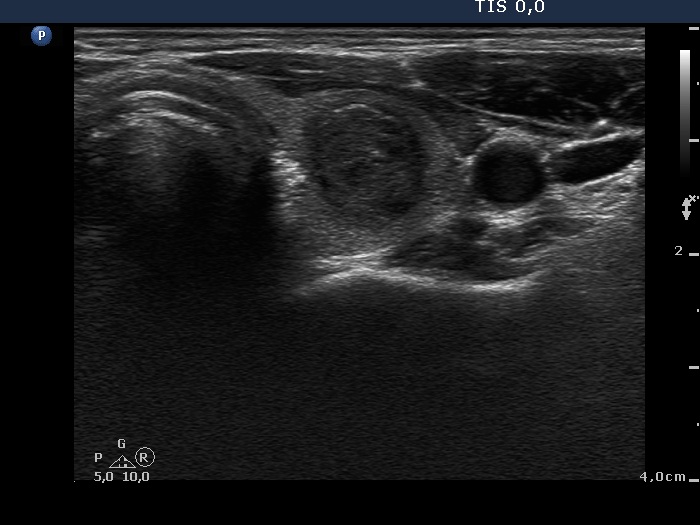

Ethanol sclerotherapy: other examples - Case 3: treatment of a gelatinous thyroid cyst

Six months after the therapy (ultrasonographic picture 1)

Right lobe, horizontal scan. The nodule decreased further.